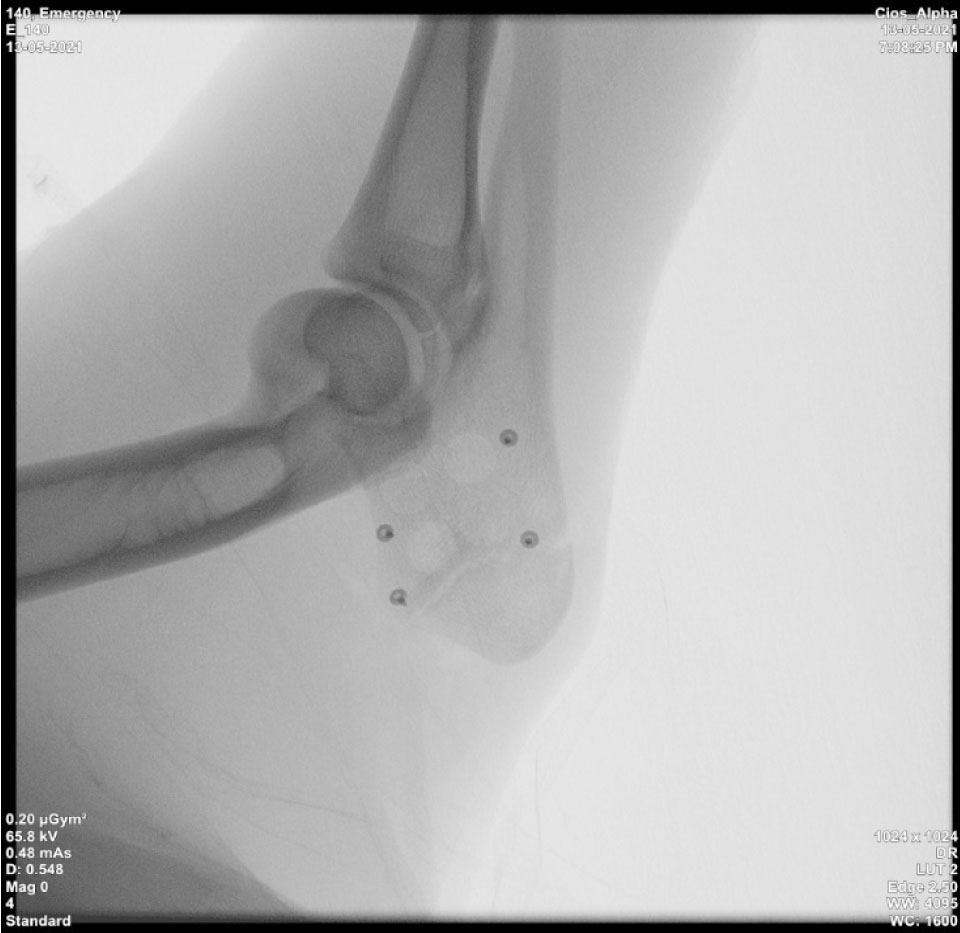

Рис. 7. Контрольная рентгенограмма локтевого отростка сразу после операции. Визуализируются 4 трепанационных отверстия, титановые пины, фиксирующие коллагеновую мембрану

После хирургического этапа проводили рентгенологический прицельный контроль в каждой области имплантации (рис. 7).